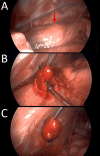

The classic clinical vignette of primary hyperparathyroidism is well described as "bones, stones, abdominal moans, and psychiatric overtones" to reflect the effects of excess parathyroid hormone (PTH) and calcium. Most commonly, primary hyperparathyroidism is due to a functional parathyroid adenoma situated by the thyroid gland. Rarely, the primary focus of autonomously produced PTH is located ectopically within the mediastinum. A 19-year-old Caucasian female with no relevant past medical history presented to the emergency department with tachycardia, nausea, vomiting, and a five-day history of vague, mid-abdominal pain. Initial computed tomography (CT) with contrast of the abdomen and pelvis was negative for acute findings, and she subsequently underwent biochemical screening. The patient was found to have elevated serum calcium and PTH, raising suspicion for the diagnosis of primary hyperparathyroidism. Further evaluation for a parathyroid adenoma was negative by a CT scan of the neck and thyroid ultrasound. A nuclear medicine parathyroid single-photon emission computed tomography (SPECT)/CT with technetium (Tc) 99m sestamibi found an abnormal nodular uptake within the left prevascular mediastinum suggestive of an ectopic parathyroid adenoma. A left-sided, video-assisted thoracoscopic surgery (VATS) with successful excision of the ectopic mediastinal parathyroid adenoma was performed. Surgical pathology revealed that the parathyroid adenoma was completely excised and surrounded by thymus and adipose tissue. The patient tolerated the procedure well and was discharged without further complications. The rarity of mediastinal, intrathymic parathyroid adenomas resulted in delayed diagnosis in this patient, understandably so as errant embryogenesis does not occur commonly. Visualization with SPECT/CT and successful specimen excision by minimally invasive VATS resulted in the accurate diagnosis and ultimate cure of this patient's primary hyperparathyroidism.